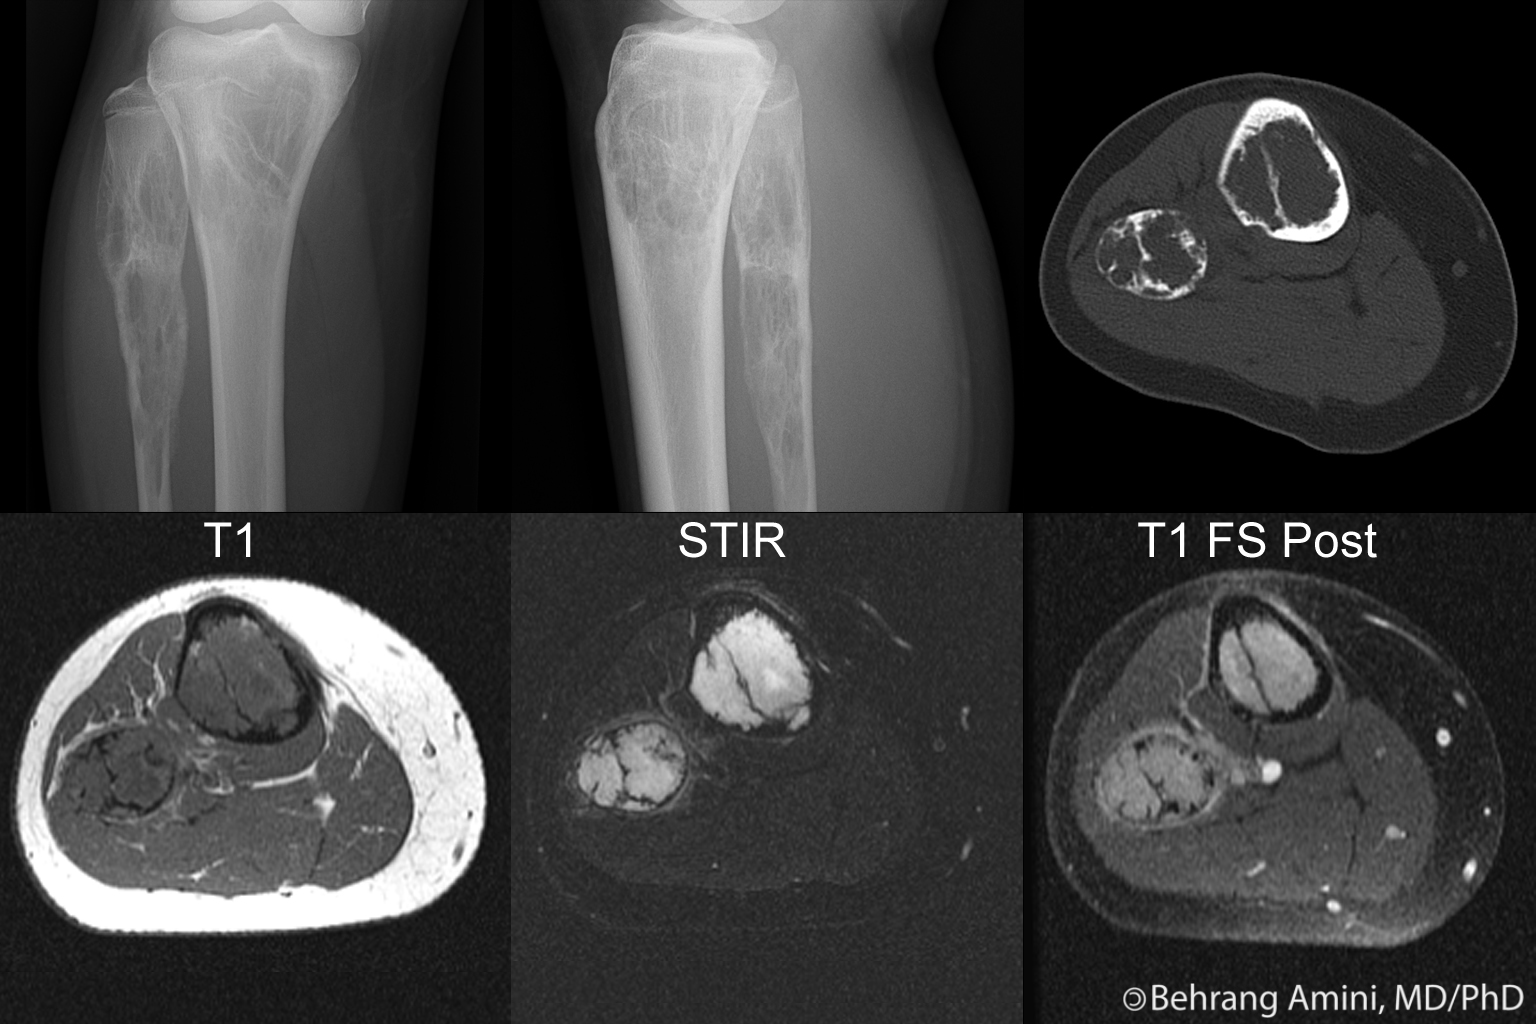

Medullary osseous hemangiomas occur most commonly in the diaphysis (48% of cases), with metadiaphyseal (30%), metaphyseal (12%), metaepiphyseal (4%), epimetadiaphyseal (3%) and epiphyseal (1%) lesions occurring less commonly. On radiographs, medullary lesions can have corduroy and radiating trabecular thickening similar to those seen in the vertebral bodies and skull, respectively, but this is an uncommon presentation. A more common appearance is a bubbly pattern of bone lysis that creates a honeycomb, lattice-like, or "hole-within-hole" appearance. This bone lysis can appear as linear and circular densities on radiographs, representing vascular channels seen longitudinally and en face, respectively. The appearance can mimic that of lymphoma, osteomyelitis and metastatic disease.

On CT, medullary hemangiomas appear as expansile lytic areas surrounded by coarse trabecular bone. A "polka dot" appearance, when seen, can suggest the diagnosis.

On MRI, the vascular channels are hypointense on T1-weighted images and hypointense to very hyperintense on T2-weighted images depending on the speed of blood flow. The trabeculations may be seen as areas of low signal.